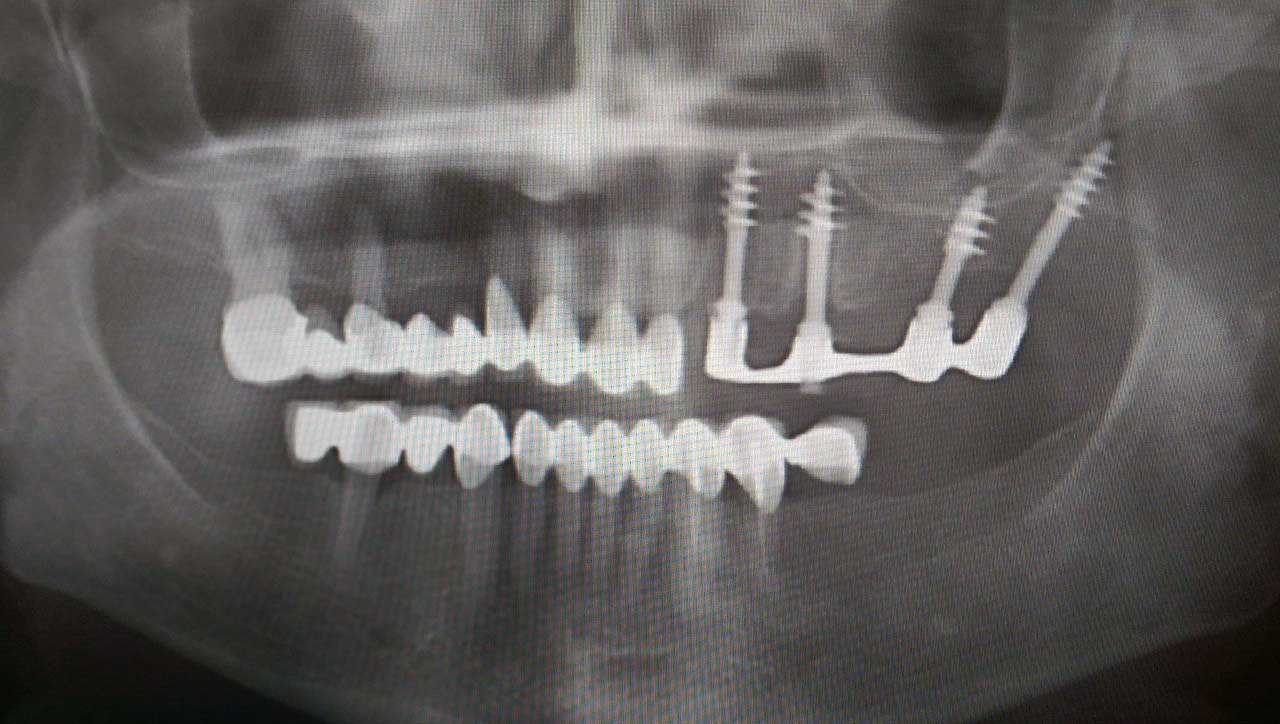

Elhanyagolt fogsor cseréje 2 nap alatt

2 nap alatt varázsoltuk ezt a szép esztétikus alsó, felső körhídat implantátumokkal megtámasztva a korábban elhanyagolt szájba. Az 1. nap 26 fogat távolítottunk el, mert annyira rossz állapotban voltak, és rögtön azonnal terhelhető IHDE svájci implantátumokat raktunk be, fentre 8, lentre 6 darabot. A sebeket összevarrtuk és intraorális szkennerrel digitális lenyomatot vettünk. 2 nap múlva pedig beragasztottuk a kész PMMA műanyag körhidakat. Dr. Kelemen Péter és a Symbion Fogtechnika munkája.